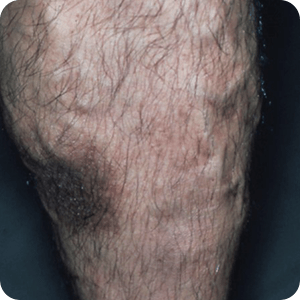

静脈瘤によるうっ滞性皮膚炎

遺伝的に静脈の弁が弱い体質に加えて、長時間・長期間の立ち仕事、肥満、加齢、出産などが誘因となって膝下3分の1の部位に静脈瘤ができ、血液のうっ滞が生じます。

血液がうっ滞すると、血管から皮膚への酸素や栄養の供給が不足し、皮膚炎や色素沈着などの症状が出ると考えられています。

静脈瘤の病気が進行すると、皮膚に色がついてしまったり(色素沈着)、足のくるぶしの上のところの皮膚が炎症を起こしたり(静脈うっ滞性皮膚炎)、重症の場合は皮膚に欠損(潰瘍)を形成してしまう(うっ滞性潰瘍)ため注意が必要です。